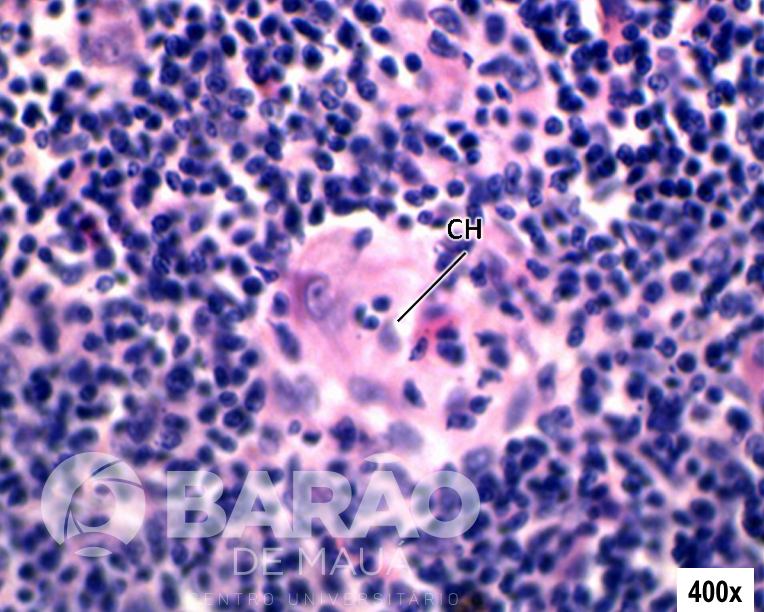

Timo - CC = camada cortical, CM = camada medular e CH = corpúsculo de Hassall - Coloração: TM

Timo - CC = camada cortical, CM = camada medular e CH = corpúsculo de Hassall - Coloração: TM.